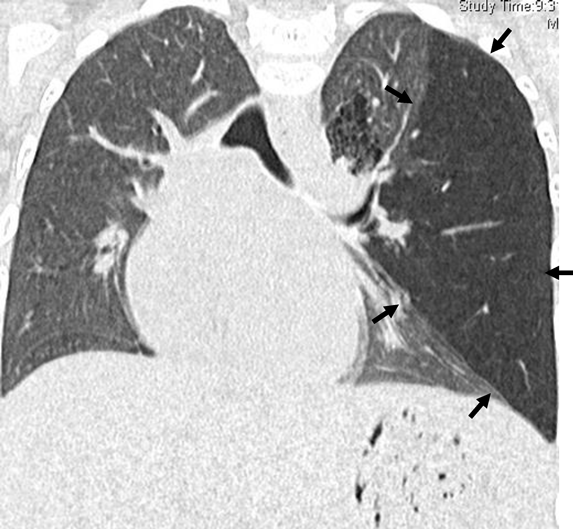

A Pediatric Case of Pulmonary Hypertension Associated with Congenital Bronchial Atresia